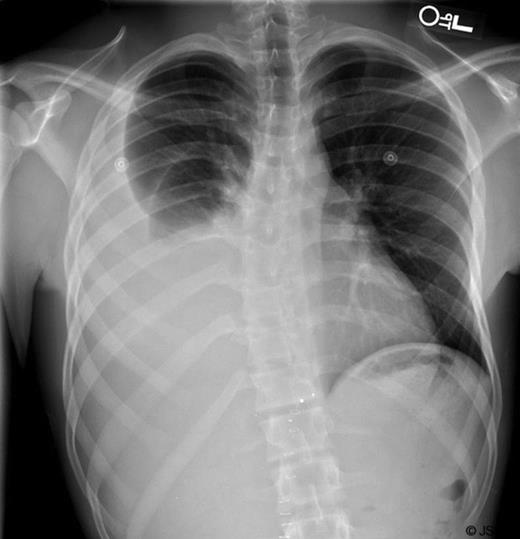

An 18 year-old-male patient presented to our trauma center following a gun shot wound to the abdomen. On arrival, he was found to have a penetrating injury to the epigastrium with no apparent exit wound. He was hemodynamically stable and a CXR demonstrated a metallic foreign body in the upper abdomen. On physical exam, he was tender to palpation. The patient was taken to the operating room for an emergency laparotomy. During surgery, a laceration of the liver was identified and repaired with omental packing (Figure 1). A large bullet fragment was palpable within the injured segment of liver and was removed. The patient had an uneventful recovery and was discharged home on post-op day 3.

Liver injury with cavitary defect (A). Repair with Omental packing (B).

Six days later, the patient returned to the emergency department with complaints of right sided chest pain and worsening dyspnea. A plain chest film was performed (Figure 2) and demonstrated a large right pleural effusion. Computerized tomography of the abdomen also demonstrated several tiny retained metallic fragments embedded within the liver and retroperitoneum (Figure 3). A chest tube was inserted on the right side and immediately drained 2.2L of milky fluid (Figure 4).